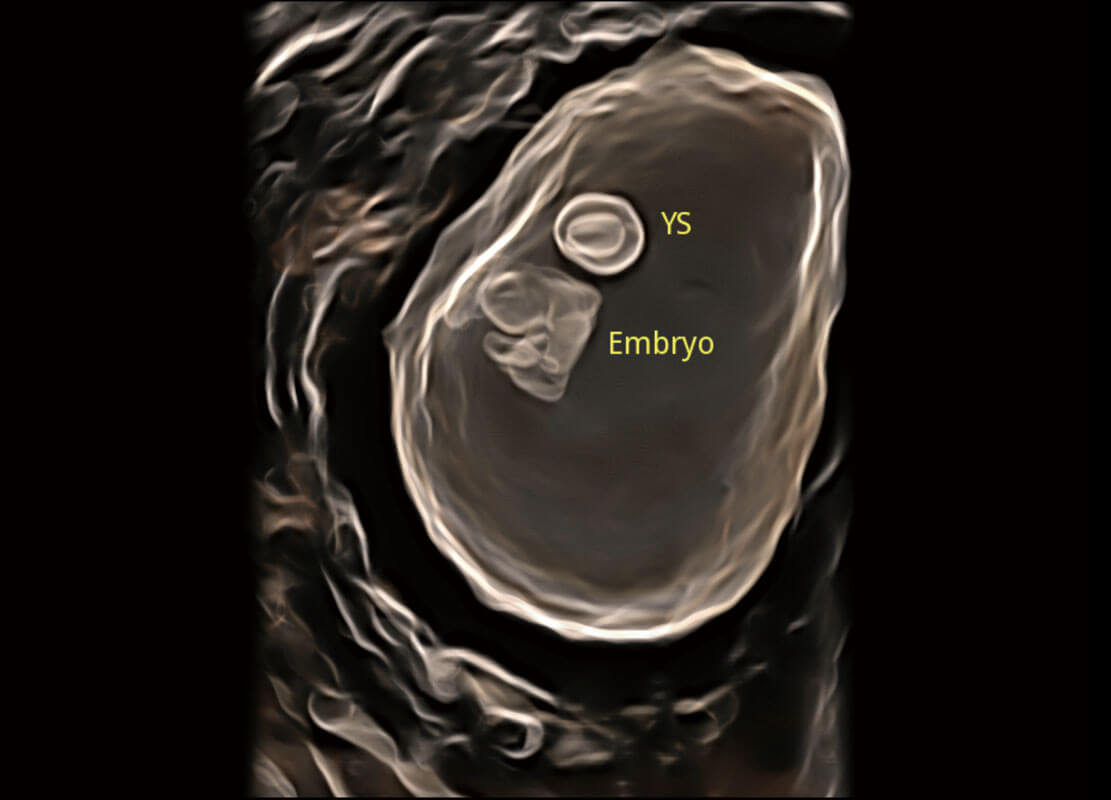

光影成像-孕囊

高分辨率容积成像-早孕胎儿